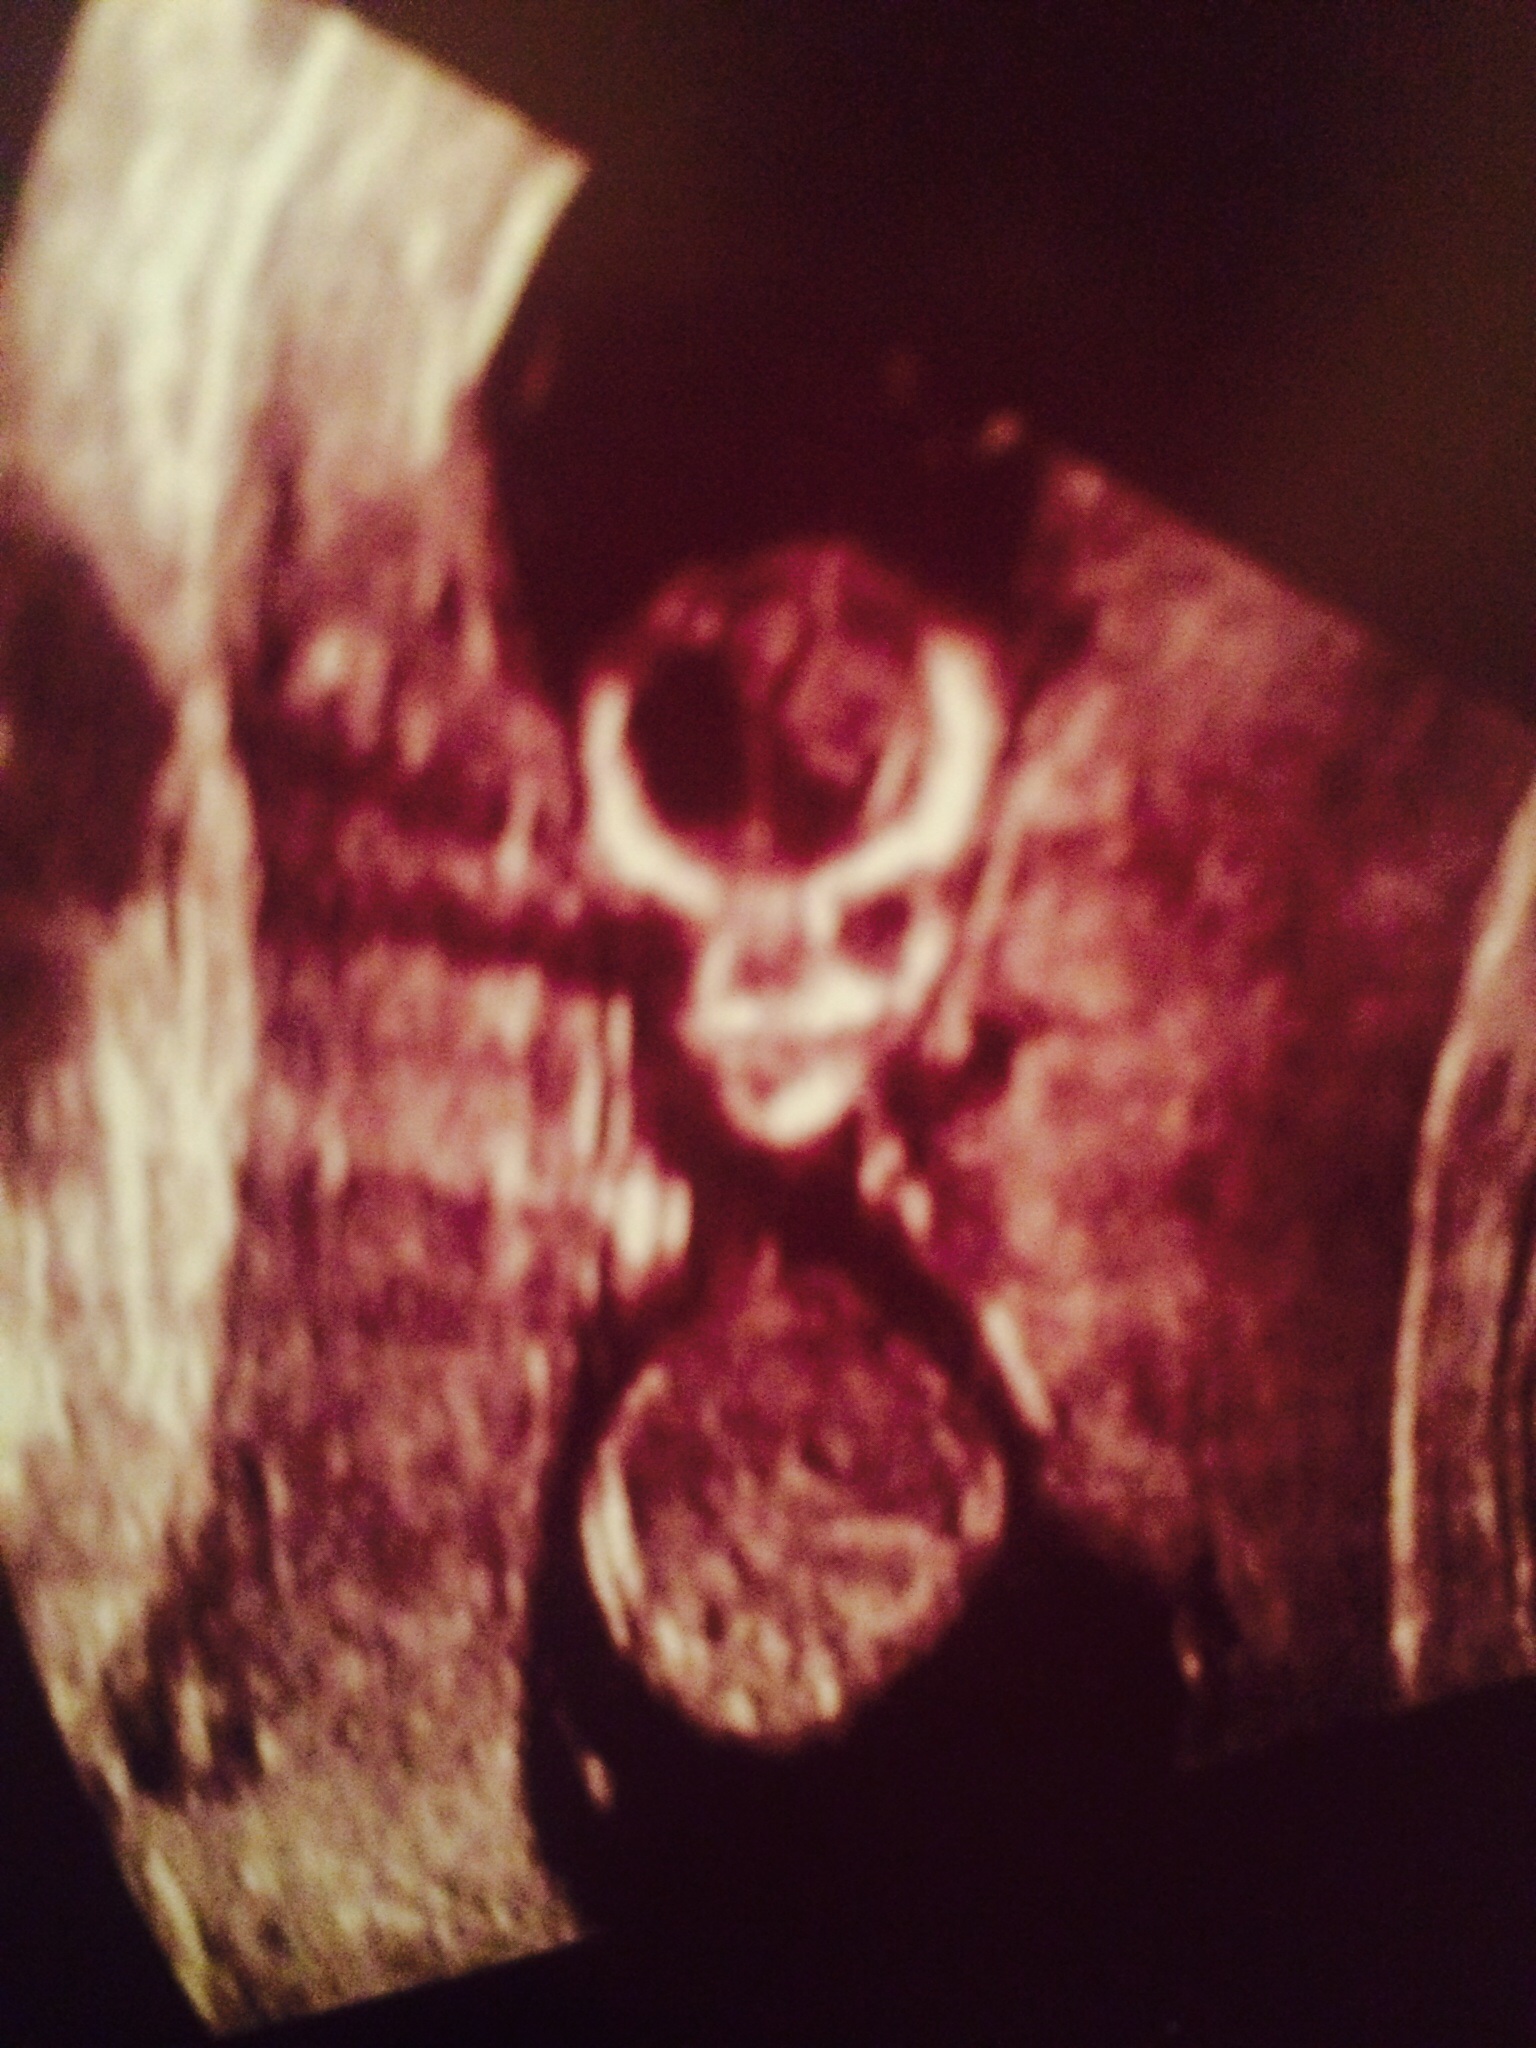

Attachment 30951Attachment 30952Attachment 30953Would love some guesses on gender please! I have a scan in 10 days so will update! Xx

Not a very clear nub shot (if it is a nub at all) but I'm getting pink vibes